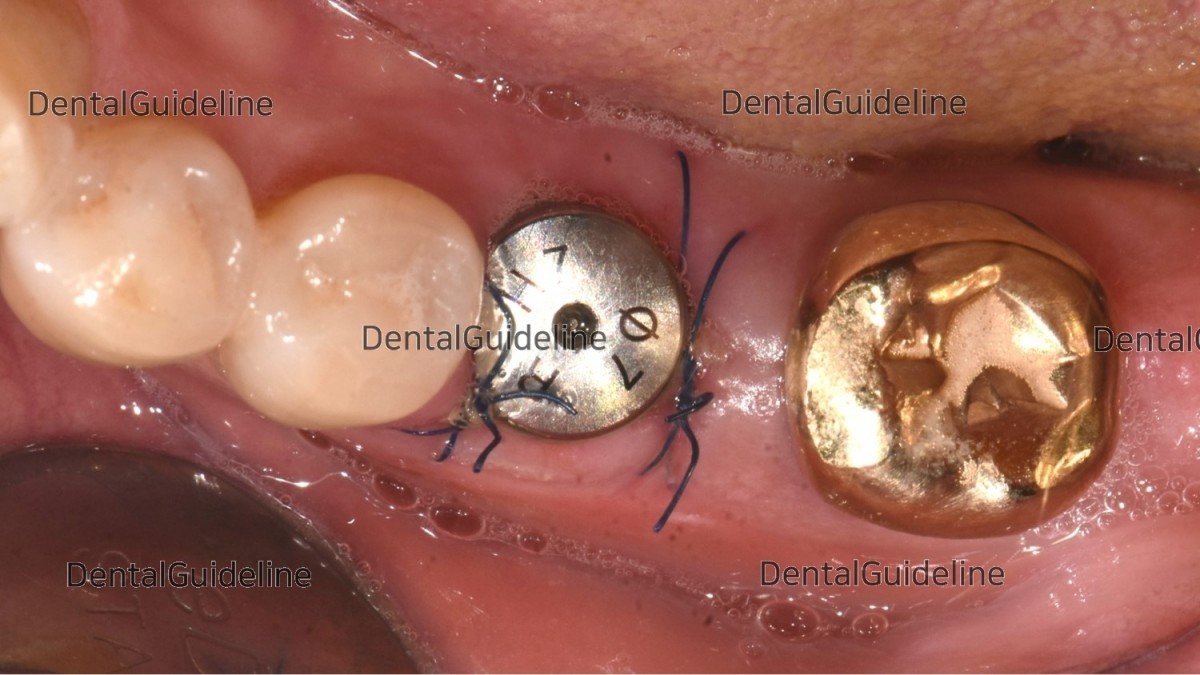

suture (blue nylon).

2weeks after the placement.